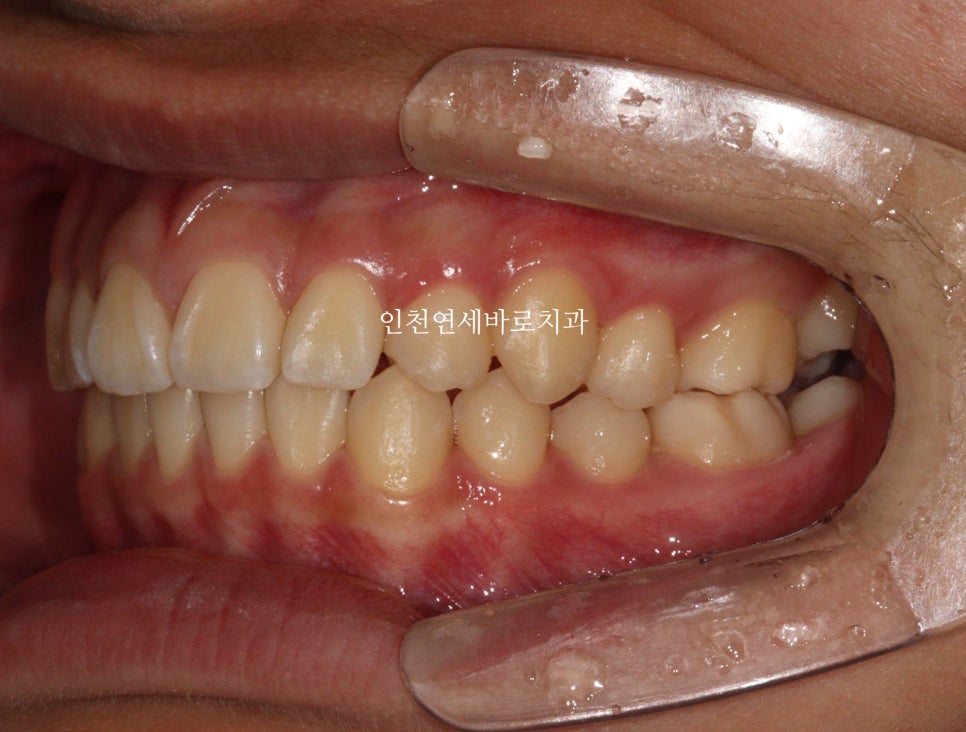

교합도 양호합니다.

최후방 어금니는 맹출 중 입니다.

화살표 부분의 치아 순서가 일반적인 순서와는 조금 다르지만

기능적, 심미적으로 거의 문제없이 해결했습니다.